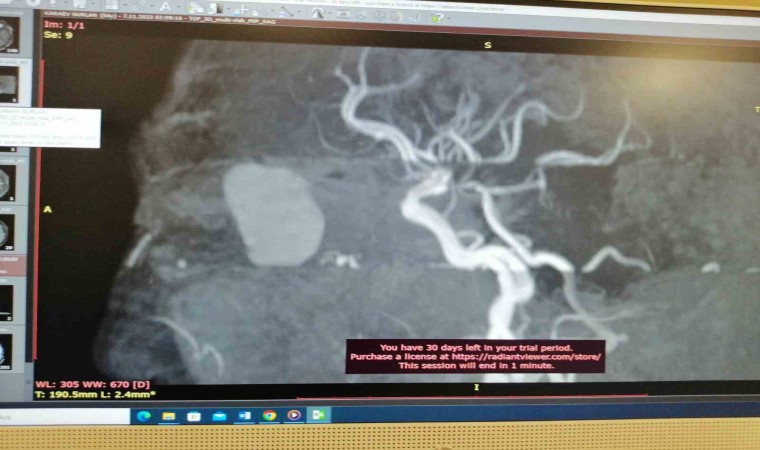

Yaptıkları tetkiklerde Karayev’in gözünde ciddi derecede görme kaybı olduğunu belirlediklerini kaydeden Uysal, “Tomografi ve MR’lar çekildi. Gözün arkasında orbita dediğimiz yerde kitle olduğu görüldü. Ona yönelik tedaviye başlandı. Bu tedavi olmasaydı, kitle görme sinirine bastığı için muhtemelen göz kör olacaktı. Aynı zamanda bu mukosel beyine doğru ilerleyecekti, daha büyük hasarlar verecekti” diye konuştu.

Hastaya mukosel tanısı konduktan sonra tedaviye başladıklarının altını çizen Uysal, "Sonra cerrahi olaraktan endoskopik sinüs cerrahisi var. Burundan girilerek göz arkasındaki kitleye ulaşıldı. Göz, orbita dediğimiz alandaki kitle çıkarıldı. Operasyonumuz 1,5 saat sürdü. Hastamızın şu an sağlık durumu gayet iyi. Artık sadece takip sürecimiz olacak" dedi.